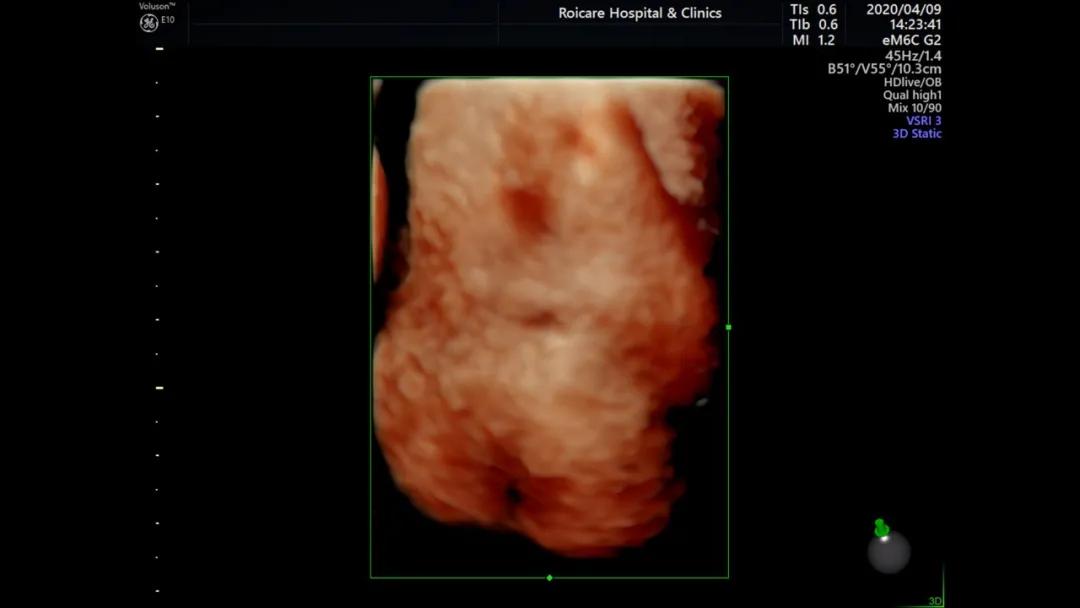

骶尾部脊柱裂伴脊髓脊膜膨出